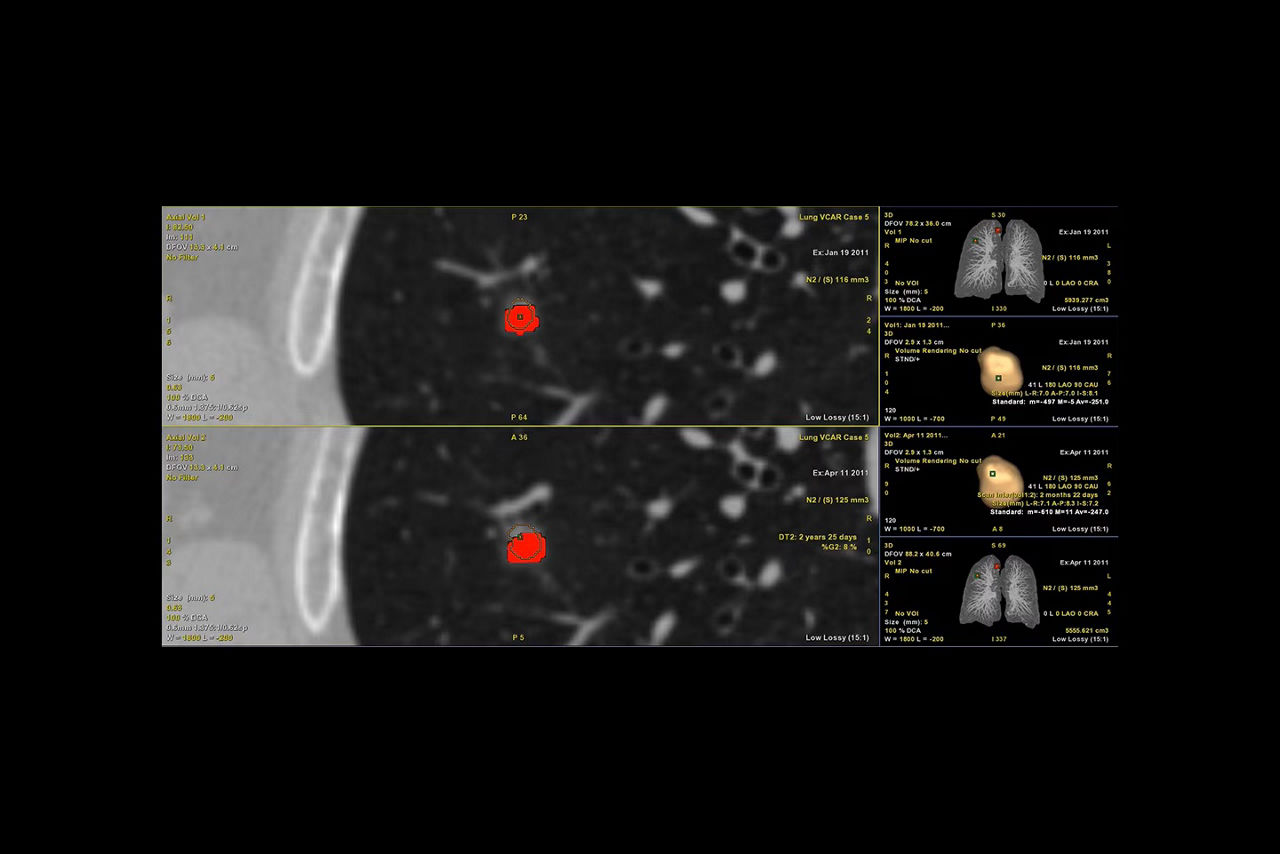

Efficient CT lung nodule assessment, diagnosis and follow-up.

Automatic nodule segmentation

Provides automated segmentation and sizing of all nodules types

Automatic nodule analysis

Provides nodule information such as % growth, doubling time and volumes